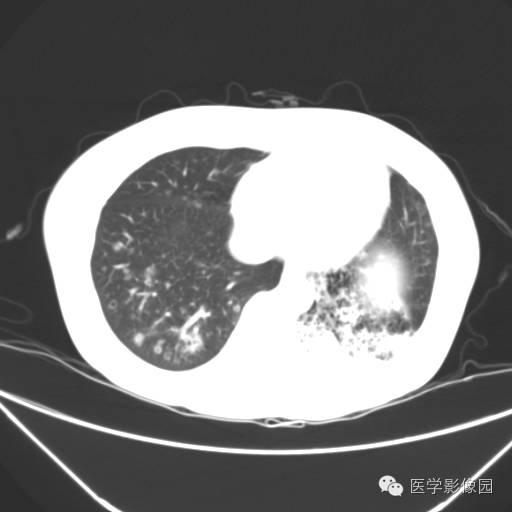

肺叶实变性支气管肺泡癌1例CT影像表现